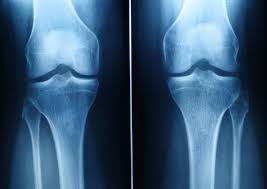

Can damaged cartilage be fixed? Glucosamine glucosamine is found naturally in the body, though it can also be obtained from shrimp, crab, and lobster. When damaged in the joints, it can lead to pain, inflammation, limited range of motion and stiffness that can eventually progress to osteoarthritis (oa)the most common type of arthritis. See full list on arrowheadhealth.com As stated throughout the article, most people will not be able to fully treat their osteoarthritis through food alone. Jul 27, 2015 · foods rich in vitamin a stimulate cartilage regeneration on the hip and knee. Jul 01, 2018 · you could definitely use these foods and exercise to repair the damaged cartilage naturally. Nutreance.com has been visited by 10k+ users in the past month

Hyaluronic acid can be produced naturally in your body but the ability decreases as you age. Vitamin k is essential for bone and joint health. See full list on arrowheadhealth.com See full list on arrowheadhealth.com Find knee cartilage injury help here. More images for how to build cartilage in knee naturally » Dark green and leafy vegetables. Remember when your mom used to force you to eat those green leafy vegetables? Glucosamine glucosamine is found naturally in the body, though it can also be obtained from shrimp, crab, and lobster. Here is a list of foods that help rebuild cartilage. Nutreance.com has been visited by 10k+ users in the past month Luckily, it is found in many foods, being especially abundant brussels sprouts. Hence eating foods rich in vitamin c and hyaluronic acid can help to boost collagen production in your body more efficiently hence knee cartilage will be benefited.